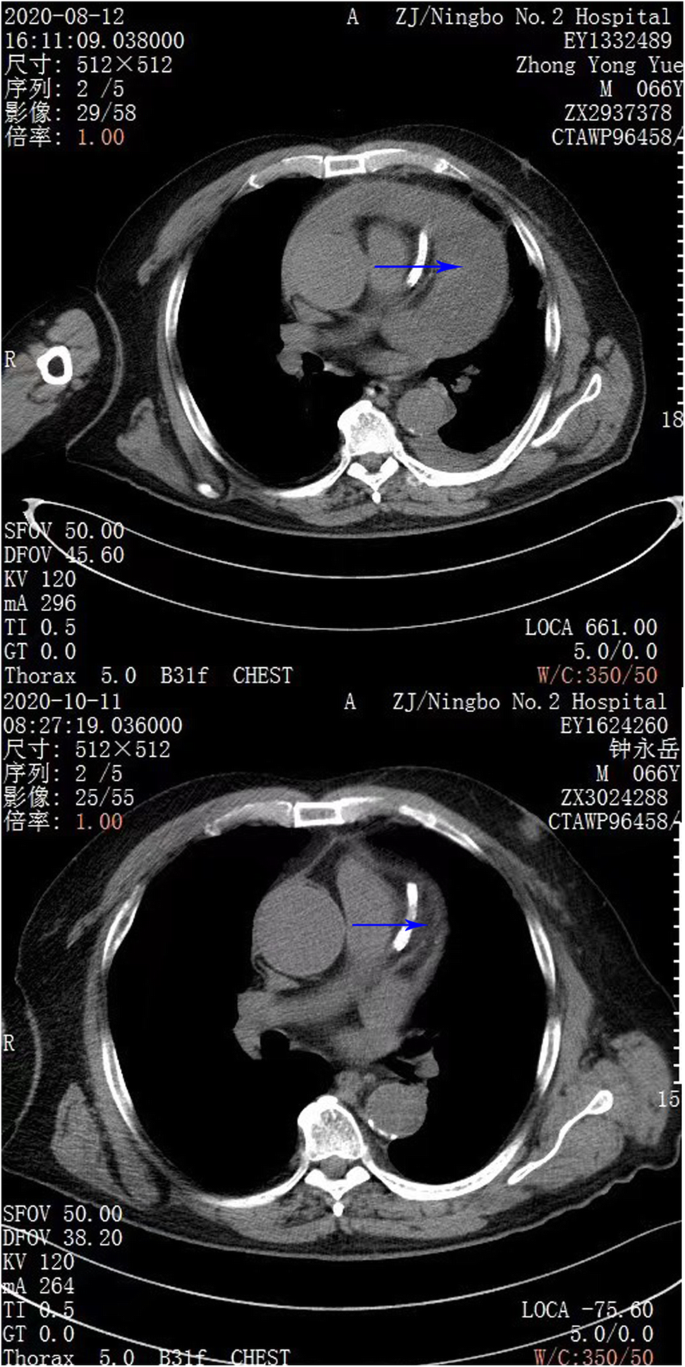

The pericardium was caught by double joint oval forceps and lift up. After the blood clot under the incision was excavated by another double joint oval forceps, the thoracoscope was inserted into the pericardial cavity through the pericardial incision. Take the advantage of the 30°slope of the thoracoscope, we can observe different directions by turn the scope without move the shaft. To obtain a better view, we used a curved double joint forceps to enlarge the pericardial cavity by using the turning of the forceps to lift the pericardium. After cleaning the left part of the pericardial cavity, we turn the scope to the anterior and right lateral cavity to clean the blood clot until the level of superior vena cava. It is hard to avoid squeezing the heart during the procedure, so the ECG(Electrocardiogram) and blood pressure must be payed attention to during the operation. A drainage tube was insert into the pericardial cavity and the incision was sutured in layers. Another drainage tube was placed in the pleural space under direct vision and connected to underwater seal. The postoperative course was uneventfull. He was discharged 7 days after the operation. A chest CT on October 11th showed there was almost no pericardial effusion left (Fig. 1, Fig. 2).